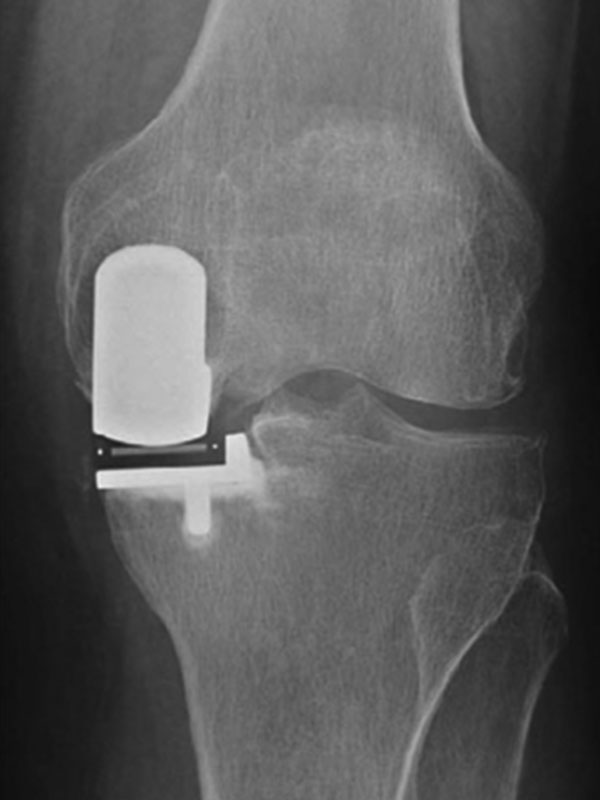

무릎관절 내측면 절반만 관절염이 있을 때, 해당 구획만 인공관절로 바꿔주는 방법입니다. 무릎의 구조상 주로 안쪽 관절면의 퇴행성관절염이 발생하며, 바깥쪽 연골은 상대적으로 잘 유지되는 경우가 많습니다. 이런 상황에서 마모가 진행된 안쪽면 절반만 부분인공관절로 교체하고, 다른 구획의 구조물은 본인의 것을 유지하는 치료법이 ‘무릎 인공관절 반치환술(부분치환술)입니다.

최소피부절개(10cm 이하)로 손상된 무릎관절의 일부를 제거하고, 내측면만 인공관절로 바꿔주는 치료법으로 기존의 전치환술에 비해 회복속도가 빠르며, 수혈이 필요없고, 입원기간이 짧습니다. 관절의 움직임이 자유롭다보니 수술후 무릎을 강제로 꺾는 재활치료가 필요없으며, 다른 구획들의 연골,인대,연골판 등을 손상없이 보존함으로 정상적인 무릎관절로 회복이 가능하며, 일상생활로의 복귀도 빠릅니다.

반치환술이 가능한지 판단하기 위해서는 MRI와 같은 정밀검사를 통해 연골 손상과 마모상태를 파악하며, 다른 구획에 문제가 없는지 확인하며, 전방십자인대나 측부 인대, 외측 반월상 연골판의 손상여부를 함께 확인하게 됩니다. 전치환술과 달리 반치환술(부분 치환술)의 경우, 손상된 구획만을 인공관절로 교체하며 그 외 십자인대 및 측부인대 다른 구획의 관절의 상태가 정상적이라 수술후에도 훨씬 더 부드러운 움직임이 가능하고 회복도 빠르며, 스포츠 활동이나 여가활동, 직장생활 등이 가능하여, 정상적인 관절로 생활할 수 있습니다.

63세 여성 ㅣ 퇴행성관절염 ㅣ 인공관절 전치환술

증 상

오래된 양 무릎 통증으로 그동안 아플 때마다 주사치료,약물치료를 시행함. 최근에는 약물치료, 주사치료에도 차도가 없이 지속적으로 무릎통증이 발생하며, 쉴 때도 통증이 생김. 조금만 걸어도 아파서 무릎에 손이 가며, 활동하기 힘들어 절뚝거리며 걷거나 보행기에 도움을 받음.

치료

검사상 켈그렌 로렌스 4단계로 퇴행성관절염 말기에 해당. 그동안 꾸준하고, 지속적인 보존적 치료에도 차도가 없어 양쪽 인공관절 전치환술 시행함.

경과

하반신마취, 수면유도하에 1시간정도의 수술시간이 소요됨. 한쪽 인공관절수술후 다음날부터 보행을 바로 시작하며, CPM운동기구를 통한 재활치료를 병행함. 1주뒤 반대편 인공관절 수술을 시행하였으며, 총 입원기간은 3주정도 소요되었음.(한쪽 수술 후 실밥제거까지 2주정도 시간이 소요되며, 병원에서 실밥제거후 퇴원시 2주정도 입원기간이 소요되며, 피검사나 수술상처가 양호하면 수술후 1주째도 퇴원이 가능함). 관절재활운동은 집에서 시행하였으며 통증없이 잘 회복함.